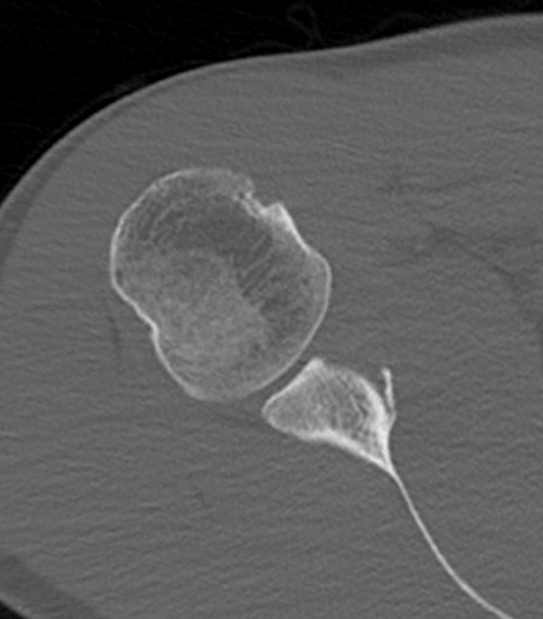

Case 1: Failed Latarjet